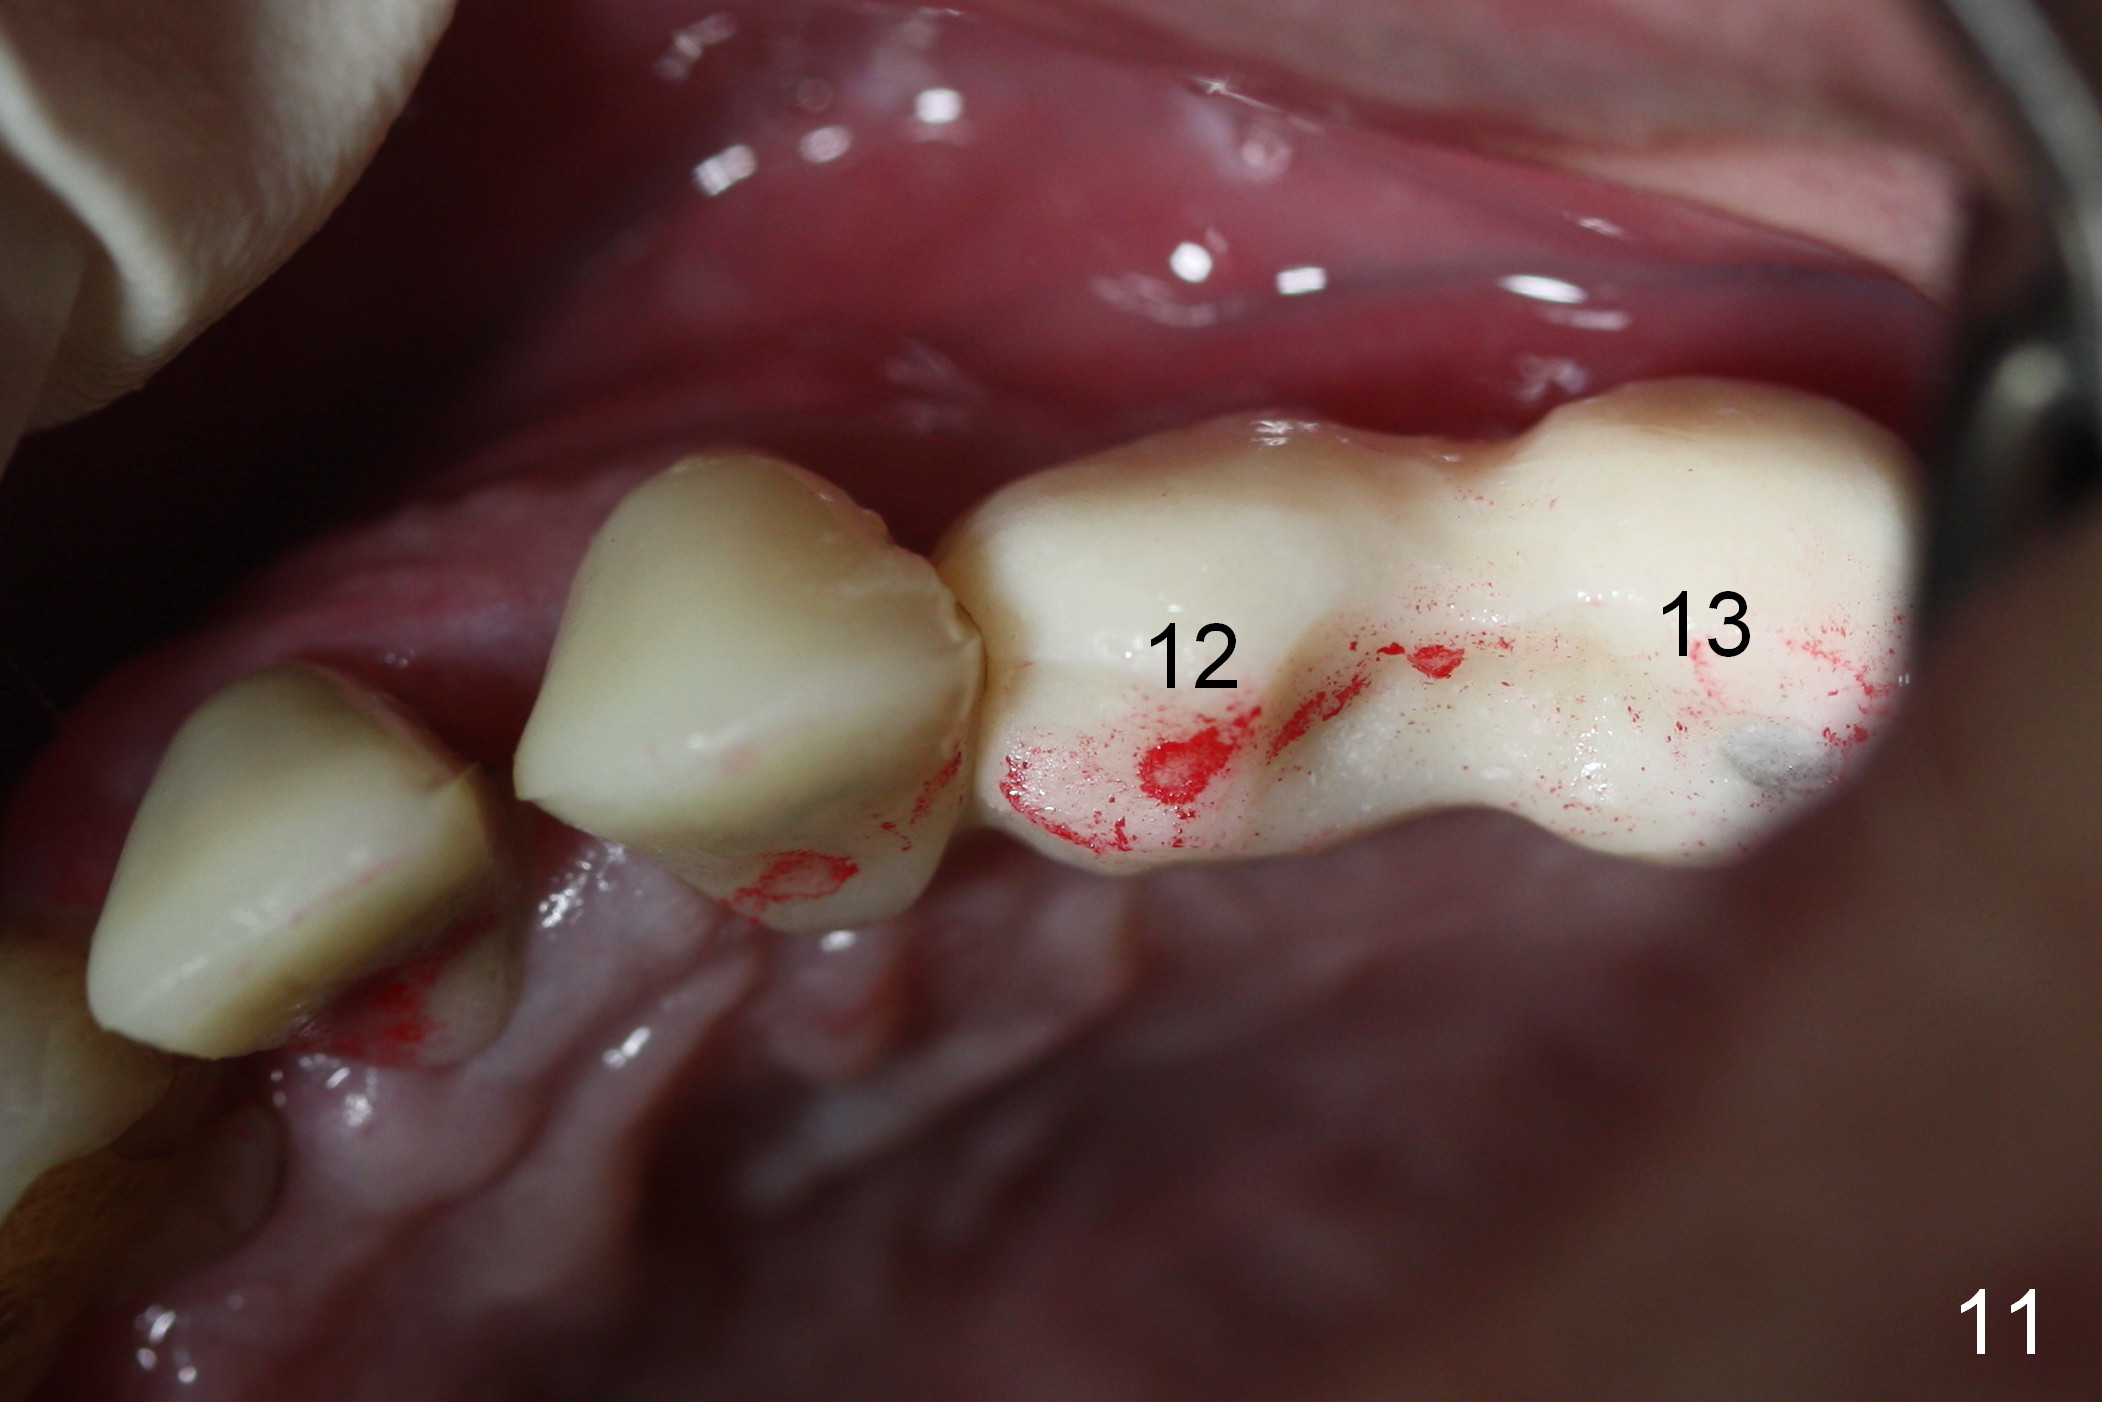

When the patient returns for implant placement (2nd visit after initial exam), he reveals that he is a dental phobic. He requests placement of 4 implants in the upper left quadrant, instead of 2. Narrow ridge is unexpected in the canine and premolar area (Fig.1). Limited bone height at #13 (Fig.3 arrowheads: sinus floor) is found when initial drills are in place (Fig.2,3). A 2-piece implant (4.5x17 mm tissue-level) is placed at #10 after extraction, while 1-piece implants are placed at 11 (3x17 mm (tissue-level, 15 °) and 12 and 13 (bone-level, 2.5x14, 12 mm, respectively; Fig.4,5). In fact the 1 piece implant at #13 is not completely placed (Fig.5). It is removed, the apical 3 threads are cut off (Fig.6 <, since a shorter implant was unavailable in the office) and the remaining implant is re-inserted. The insertion torques of the 4 implants are ~ 60, ~ 35, < 35 and 15 Ncm, respectively. After adjustment (Fig.7), immediate provisionals are fabricated at #10 and 11 (Fig.8, later splinted with composite), while perio dressing is applied around the implants at #12 and 13 and the provisionals at #10 and 11. There is no nasal hemorrhage postop. Although the perio dressing is loose 1 week postop (Fig.9), it is not removed. When the upper lip fissure (Fig.9 <) heals, provisionals at #12 and 13 are planned to be splinted to the other two ones. Two weeks postop, the upper lip fissure heals, the perio dressing dislodges and the implants at #12 and 13 are stable (Fig.10). After abutment height adjustment, a splinted provisional is fabricated over these 2.5 mm 1-piece implants (Fig.11).